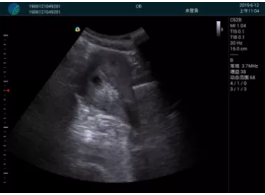

腺體內部清晰顯示一低回聲塊影,形態(tài)不規則,邊界模糊,邊緣呈毛刺狀,內部見(jiàn)砂礫樣鈣化

M20引導下穿刺活檢術(shù)

M20引導下平面內穿刺取出的腫塊組織